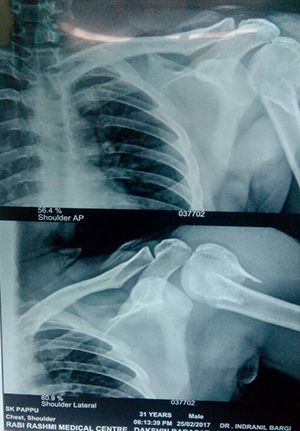

Reduction and internal fixation for proximal humerus fracture

before operation

After operation